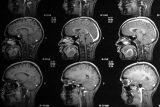

Фото: Stewart Goldstein / Reuters